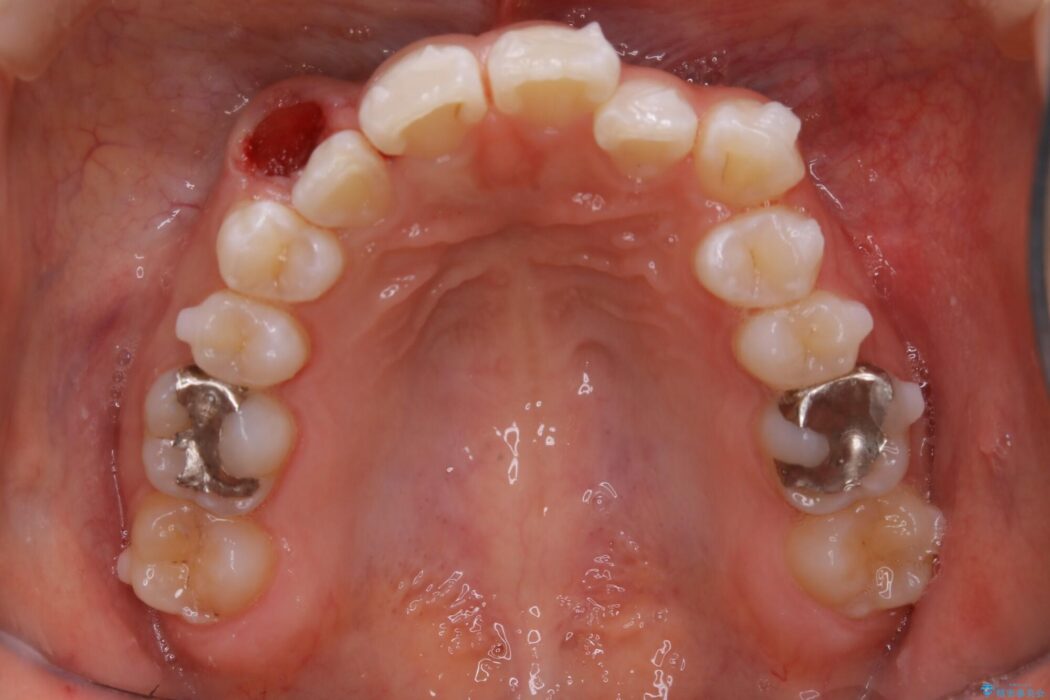

【20代女性】生まれつき歯の本数が足りない先天欠如を治療する

飛び出た八重歯による歯列のガタガタを主訴に来院されました。

診査したところ叢生だけでなく生まれつき永久歯の欠損、いわゆる先天欠如により歯の本数が少ないため噛み合わせなどにも影響が出ている状態でした。

特殊な状況からの矯正治療となるため、抜歯する本数や位置、歯列を整えるにあたって必要なスペースの確保を慎重に計画し、インビザライン コンプリヘンシブパッケージでのマウスピース矯正を行いました。

「先天欠如歯」とは「無歯症」とも呼ばれる生まれつき永久歯の数が足りない症状のことをいいます。上下合わせて乳歯は20本・永久歯は28本あるのが正常な本数となります。